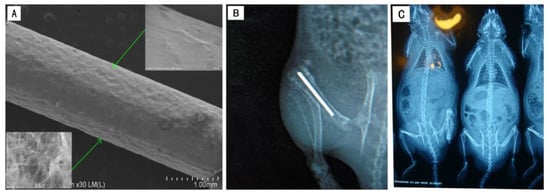

Based on an animal study explained previously [11], male Sprague-Dawley rats aged 8-weeks with each weighing between 250–300 g each were anesthetized via injection with ketamine (80 mg/kg) and xylazine (10 mg/kg). In all the samples, an implant was provided for the right femurs. After shaving, the right leg was washed with a 10 percent povidone-iodine solution. A skin incision was then used to gently expose the distal part of the femur. The femoral intercondylar fossa was then approached using a 1 cm anteromedial incision to expose the femoral intercondylar fossa. Kirschner pins (diameter, 1 mm) were drilled to create a channel from the femoral intercondylar fossa into the medullary canal at a low speed of 800 rpm. The rods were then implanted while a bacterial suspension of S. aureus (107 CFUs) was injected into the femoral canal via the perforation. Then, the holes were closed using bone wax, followed by closing the fascia and subcutaneous layers using sutures. An X-ray was then conducted postoperatively.

The post-surgical X-ray results revealed that the rods were correctly placed intramedullary in the femurs of all rats (Figure 7). During surgical procedures, none of the rats were lost. The clinical symptoms of purulent infections were shown by all animals inside the Cp–Ti group and 9 of 10 in the TNT group. None of the rats in the HA/gentamicin/TNT group had signs of infection at four weeks’ post-operation.

Figure 7. Surgical procedure and antibacterial efficacy in vivo. (A) HA/gentamicin/TNT rods (B,C) postoperative X-ray with the implanted titanium rods in the tibia of rats.